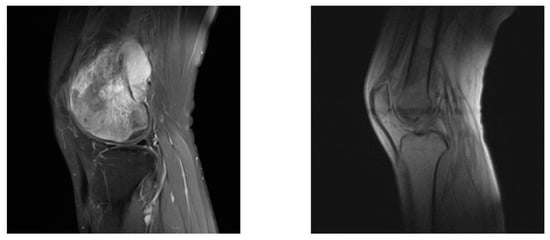

- Osteosarcoma is very difficult to diagnose. Osteosarcoma has high variability in shape and location [21,22], and the MRI images often contain redundant noise information from outside the target background, which makes it difficult for doctors to distinguish tumor tissue from surrounding normal tissue [23,24]. Most hospitals lack a complete osteosarcoma-assisted segmentation system to detect potential features of osteosarcoma images that cannot be identified with the naked eye by quantitative analysis [25].